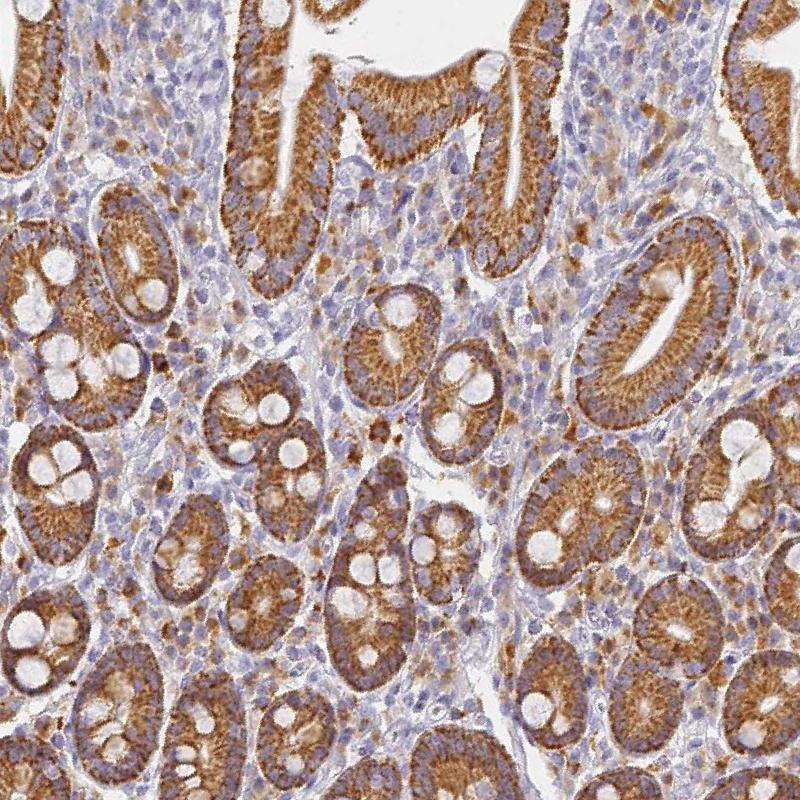

Immunohistochemical staining of human placenta shows strong granular cytoplasmic positivity in a subset of trophoblastic cells.